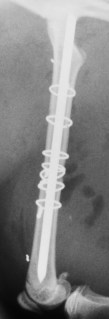

Κάταγμα μηριαίου γάτας από Πέτρος Μπεάκος13/06/201607/12/20171 σχόλιο Συντριπτικό κάταγμα διάφυσης μηριαίου οστού γάτας: οστεοσύνθεση με ήλο και σύρματα. Προσθοπίσθια ακτινογραφία Πλάγια ακτινογραφία Πλάγια ακτινογραφία μετά από οστεοσύνθεση με ήλο και σύρματα Κοινοποιήστε: Στείλε ένα σύνδεσμο σε έναν φίλο(Ανοίγει σε νέο παράθυρο) Email Εκτύπωση(Ανοίγει σε νέο παράθυρο) Εκτύπωση Mοιραστείτε στο Facebook(Ανοίγει σε νέο παράθυρο) Facebook Μοιραστείτε στο X(Ανοίγει σε νέο παράθυρο) Χ Μου αρέσει! Φόρτωση... Σχετικά